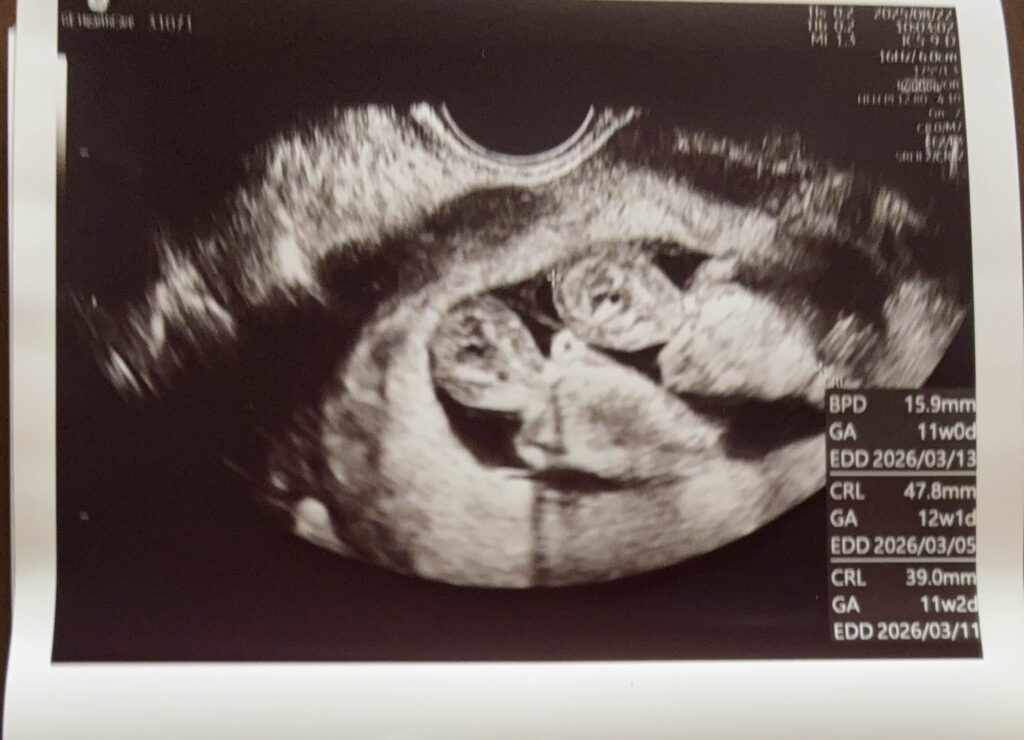

双子妊娠11週

11週で通っていた不妊治療専門CLを卒業することができました。

双子妊娠とのことで、産院ではなくNICU(新生児集中治療室)がある大きな病院へ行くように勧められ、紹介状を持って卒業しました。